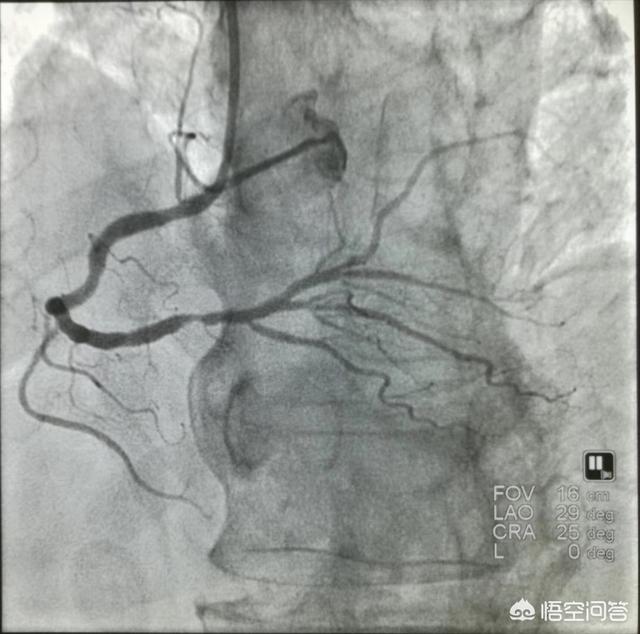

4.冠動脈造影冠動脈造影は現在でも冠動脈疾患の診断のゴールドスタンダードであるが、侵襲的で入院が必要である。

2.冠動脈造影

現在、心血管スクリーニングのゴールドスタンダードとなっているこの方法は、直感的で、介入策をタイムリーに知ることができるが、高価であり、危険でもある。

冠動脈造影

冠動脈造影検査は、冠動脈血管の走行と開存性を視覚的に観察・評価し、冠動脈病変の有無と病変の程度を評価し、左心機能を評価することができる冠動脈疾患の診断のゴールドスタンダードであり、これに基づいて冠動脈病変の程度に応じたインターベンション治療を実施し、冠動脈バイパス術やインターベンション後の治療効果を評価することができる。侵襲的診断法である冠動脈造影検査には、ヨードや造影剤に対するアレルギー、重症心肺機能不全、肝腎機能不全、不整脈、電解質異常などの禁忌があり、事故を避けるために実施できない。